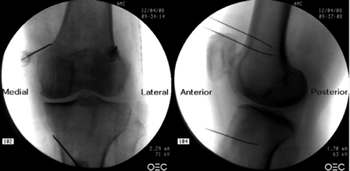

Figure 1

Figure 2

Figure 3

Figure 4